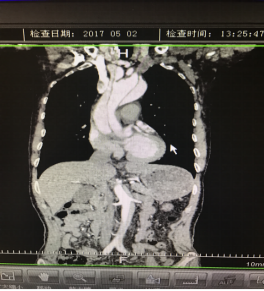

5月2號劉大伯照常早起干活,突然胸部劇烈疼痛,難以忍受,全身大汗,同時伴有右上肢發(fā)涼,他心想這次心絞痛比之前嚴(yán)重的多啊,趕緊叫上孩子到吉林國文醫(yī)院心血管內(nèi)科住院,患者長期高血壓病史,血壓一直控制不理想,大夫給他做了檢查,測左上肢血壓:82/45mmHg,右上肢血壓測不出,心率52次/分,右側(cè)肱動脈、尺動脈、橈動脈搏動消失,左側(cè)股動脈搏動較右側(cè)弱?!霸懔?,雙側(cè)血壓差別這么大,是不是主動脈夾層了?”,接診大夫趕緊找來李主任,李主任反復(fù)詢問患者病情,表情突然凝重起來,患者胸痛這么明顯,血壓低的厲害,主動脈夾層的可能性很大。二話不說,李主任立即聯(lián)系影像科的醫(yī)生準(zhǔn)備做主動脈CTA,移動患者做檢查的過程大夫們非常小心,嚴(yán)密監(jiān)測患者血壓變化情況。兩個小時后結(jié)果出來了,主動脈夾層從升主動脈一直撕裂到左側(cè)髂總動脈!??!